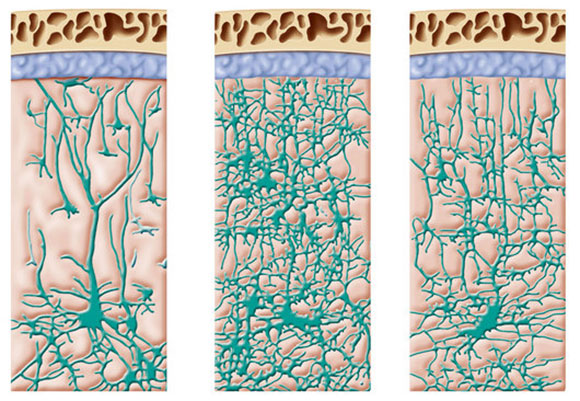

In the first years of a child’s life, the brain experiences rapid growth and development. During this period, there is a notable increase in brain volume and the complexity of connections between nerve cells. However, contrary to what some may believe, the brain's development does not halt after this early surge. Throughout our lives, redundant neural connections degenerate while new ones form in response to our activities and environmental interactions.Although the rate of growth and development diminishes over the years, the brain never ceases to change.

Throughout our lives, our brains continue to consolidate existing connections and form new ones in response to the body's activity and environmental input. Learning new skills and experiences contribute to the formation of new synapses, enabling ongoing development as thinking and learning organisms. Even in older age constant processes of transformation continue to occur in the brain. Contrary to popular belief, the generation of new nerve cells is still possible later in life, particularly in regions associated with the formation of new memories.

In the first years of a child’s life the brain grows and develops rapidly – but continues to reshape throughout life. A drawing of a cross section of a child at ages nine months (left), two years and four years | JACOPIN, Science Photo Library